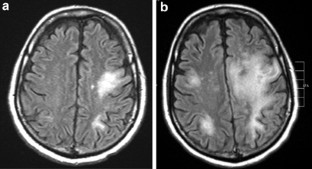

Progressive multifocal leukoencephalopathy (PML) is a rare subacute demyelinating disorder of the central nervous system (CNS) caused by the DNA JC human polyomavirus. In immunocompromised hosts, PML is caused by reactivation of a latent infection rather than de novo primary exposure. PML in the setting of hematopoietic cell transplantation (HCT) is exceedingly rare. PML should be considered in the differential diagnosis of HCT recipients, autologous or allogeneic, presenting with worsening of neurological symptoms, especially associated with post-transplant neurodegenerative findings. Although DNA polymerase chain reaction (PCR) of the cerebrospinal fluid (CSF) has emerged as a promising tool for detecting JC virus, a negative result does not rule out PML. Brain biopsy remains the most reliable and accurate method for diagnosing JC virus-associated PML. Presently, there is no universally effective antiviral therapy against JC virus and outcome is fatal in the majority of cases. We hereby describe two cases of PML developing after allogeneic HCT and provide a comprehensive review of the literature.

Mark AS, Atlas SW . Progressive multifocal leukoencephalopathy in patients with AIDS: appearance on MR images. Radiology 1989; 173: 517–520.

Kharfan-Dabaja, M., Ayala, E., Greene, J. et al. Two cases of progressive multifocal leukoencephalopathy after allogeneic hematopoietic cell transplantation and a review of the literature. Bone Marrow Transplant 39, 101–107 (2007). https://doi.org/10.1038/sj.bmt.1705548